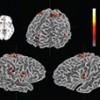

Swarms of bees and brain neurons make decisions using strikingly similar mechanisms, reports a new study in the Dec. 9 issue of Science. In previous work, Cornell University biologist Thomas Seeley clarified how scout bees in a honeybee swarm perform “waggle dances” to prompt other scout bees to inspect a promising site that has been found.